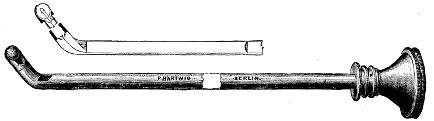

| XII. SURGERY.—Papillomatous Tumor of the Bladder, demonstrated by Means of Lister's Electro-cystoscope.—By F. N. Otis, M.D.—An interesting instance of the use of an exploratory electric light.—2 illustrations. | 10354 |

| Tumors of the Bladder Diagnosed by Means of the Electro-Endoscopic Cystoscope.—By Dr. Max Nitze.—The same general subject in further detail, giving the German practice.—5 illustrations. | 10353 |